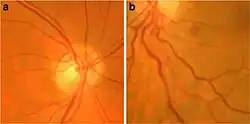

Non-muscular

The most common non-musculoskeletal manifestation of FSHD is abnormalities in the small arteries (arterioles) in the retina. Tortuosity of the arterioles is seen in approximately 50% of those with FSHD. Less common arteriole abnormalities include telangiectasias and microaneurysms.[42][43] These abnormalities of arterioles usually do not affect vision or health, although a severe form of it mimics Coat's disease, a condition found in about 1% of FSHD cases and more frequently associated with large 4q35 deletions.[2][44] High-frequency sensorineural hearing loss can occur in those with large 4q35 deletions, but otherwise is no more common compared to the general population.[2] Large 4q35 deletion can lead to various other rare manifestations.[45]

Retinopathy

Tortuosity of the retinal arterioles, and less often microaneurysms and telangiectasia, are commonly found in FSHD.[42] Abnormalities of the capillaries and venules are not observed.[42] One theory for why the arterioles are selectively affected is that they contain smooth muscle.[42] The degree of D4Z4 contraction correlates to the severity of tortuosity of arterioles.[42] It has been hypothesized that retinopathy is due to DUX4-protein-induced modulation of the CXCR4–SDF1 axis, which has a role in endothelial tip cell morphology and vascular branching.[42]